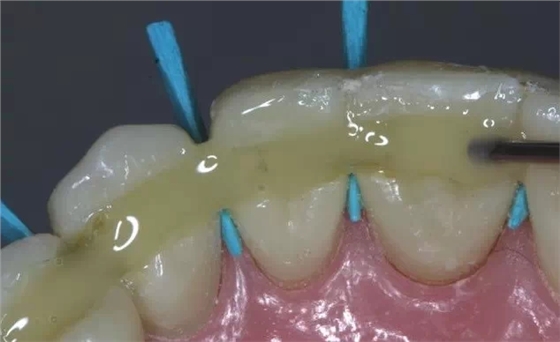

這是牙周病常規(guī)的治療方法,清除或控制臨床炎癥和致病因素,去除病因,消除炎癥。包括口腔衛(wèi)生宣教、充填齲洞、口腔潔治刮治、牙體牙髓治療、咬合調(diào)整、去除不良修復(fù)體、藥物治療(輔助手段,局部用藥效果好)、拔除治療效果不佳的牙周病患牙等。

牙周炎發(fā)展到一定階段時(shí),僅采用基礎(chǔ)治療難以取得較好療效,必須通過適時(shí)而合宜的手術(shù)治療挽救患牙,才能保持牙周組織健康,延長患牙在口腔內(nèi)的壽命,維持牙列的完整性,促進(jìn)全身健康。其手段包括齦下刮治、根面平整、牙周翻瓣術(shù)、牙齦切除術(shù)、牙周夾板固定術(shù)等。